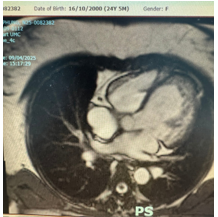

Chụp cộng hưởng từ tim có tiêm tương phản từ: Hình ảnh bệnh cơ tim thể xốp thất trái và thất phải. Phân suất tống máu thất trái (EF) = 38,34%. Tỉ lệ cơ bè/ cơ tim # 3,3.

Hình 2. Hình ảnh chụp cộng hưởng từ tim trường hợp 2

III.2. Hai trường hợp báo cáo: đều là bệnh nhân nữ, trẻ tuổi, với triệu chứng lâm sàng gợi ý của suy tim. Qua tầm soát bệnh lý tim mạch cho thấy cả hai trường hợp có kết quả siêu âm tim là giãn buồng thất trái và phân suất tống máu thất trái (EF) giảm hướng nghĩ đến bệnh cơ tim giãn. Tuy nhiên, nguyên nhân bệnh lý cơ tim giãn ở cả 2 trường hợp cần phải được xác định để có thể theo dõi và điều trị tốt hơn. Kết quả trên chụp cộng hưởng từ có tiêm tương phản từ đã cho kết quả chẩn đoán bệnh cơ tim thể xốp tâm thất trái (trường hợp 1) và cả hai tâm thất trái – tâm thất phải (trường hợp 2) với tiêu chuẩn tỷ lệ cơ bè/ cơ tim bằng 2,3 và 3,3 kèm theo suy chức năng thất trái nặng EF = 28,8% và 38,34% tương ứng với trường hợp 1 và trường hợp 2. Như vậy, chẩn đoán bệnh cơ tim thể xốp thất trái trên bệnh nhân được xác định chủ yếu dựa vào kết quả siêu âm tim gợi ý bệnh cơ tim giãn và kết quả chụp cộng hưởng từ có tiêm tương phản từ cho chẩn đoán xác định nguyên nhân với biến chứng suy tim phân suất tống máu giảm. Trường hợp 2 là một bệnh cảnh hiếm gặp của bệnh cơ tim thể xốp khi tổn thương ghi nhận ở cả hai tâm thất phải và trái. Điều trị kiểm soát biến chứng suy tim với phác đồ điều trị 4 thuốc theo khuyến cáo của Hội tim Châu Âu [10] và Bộ Y tế [11] cho thấy bệnh nhân đáp ứng tốt với điều trị. Bệnh nhân vẫn đang được theo dõi định kỳ tại Khoa Khám bệnh – Bệnh viện Đại học Y Dược Tp. Hồ Chí Minh, tiếp tục đánh giá đáp ứng điều trị suy tim, theo dõi và điều trị kịp thời các biến chứng khác có thể xảy ra.